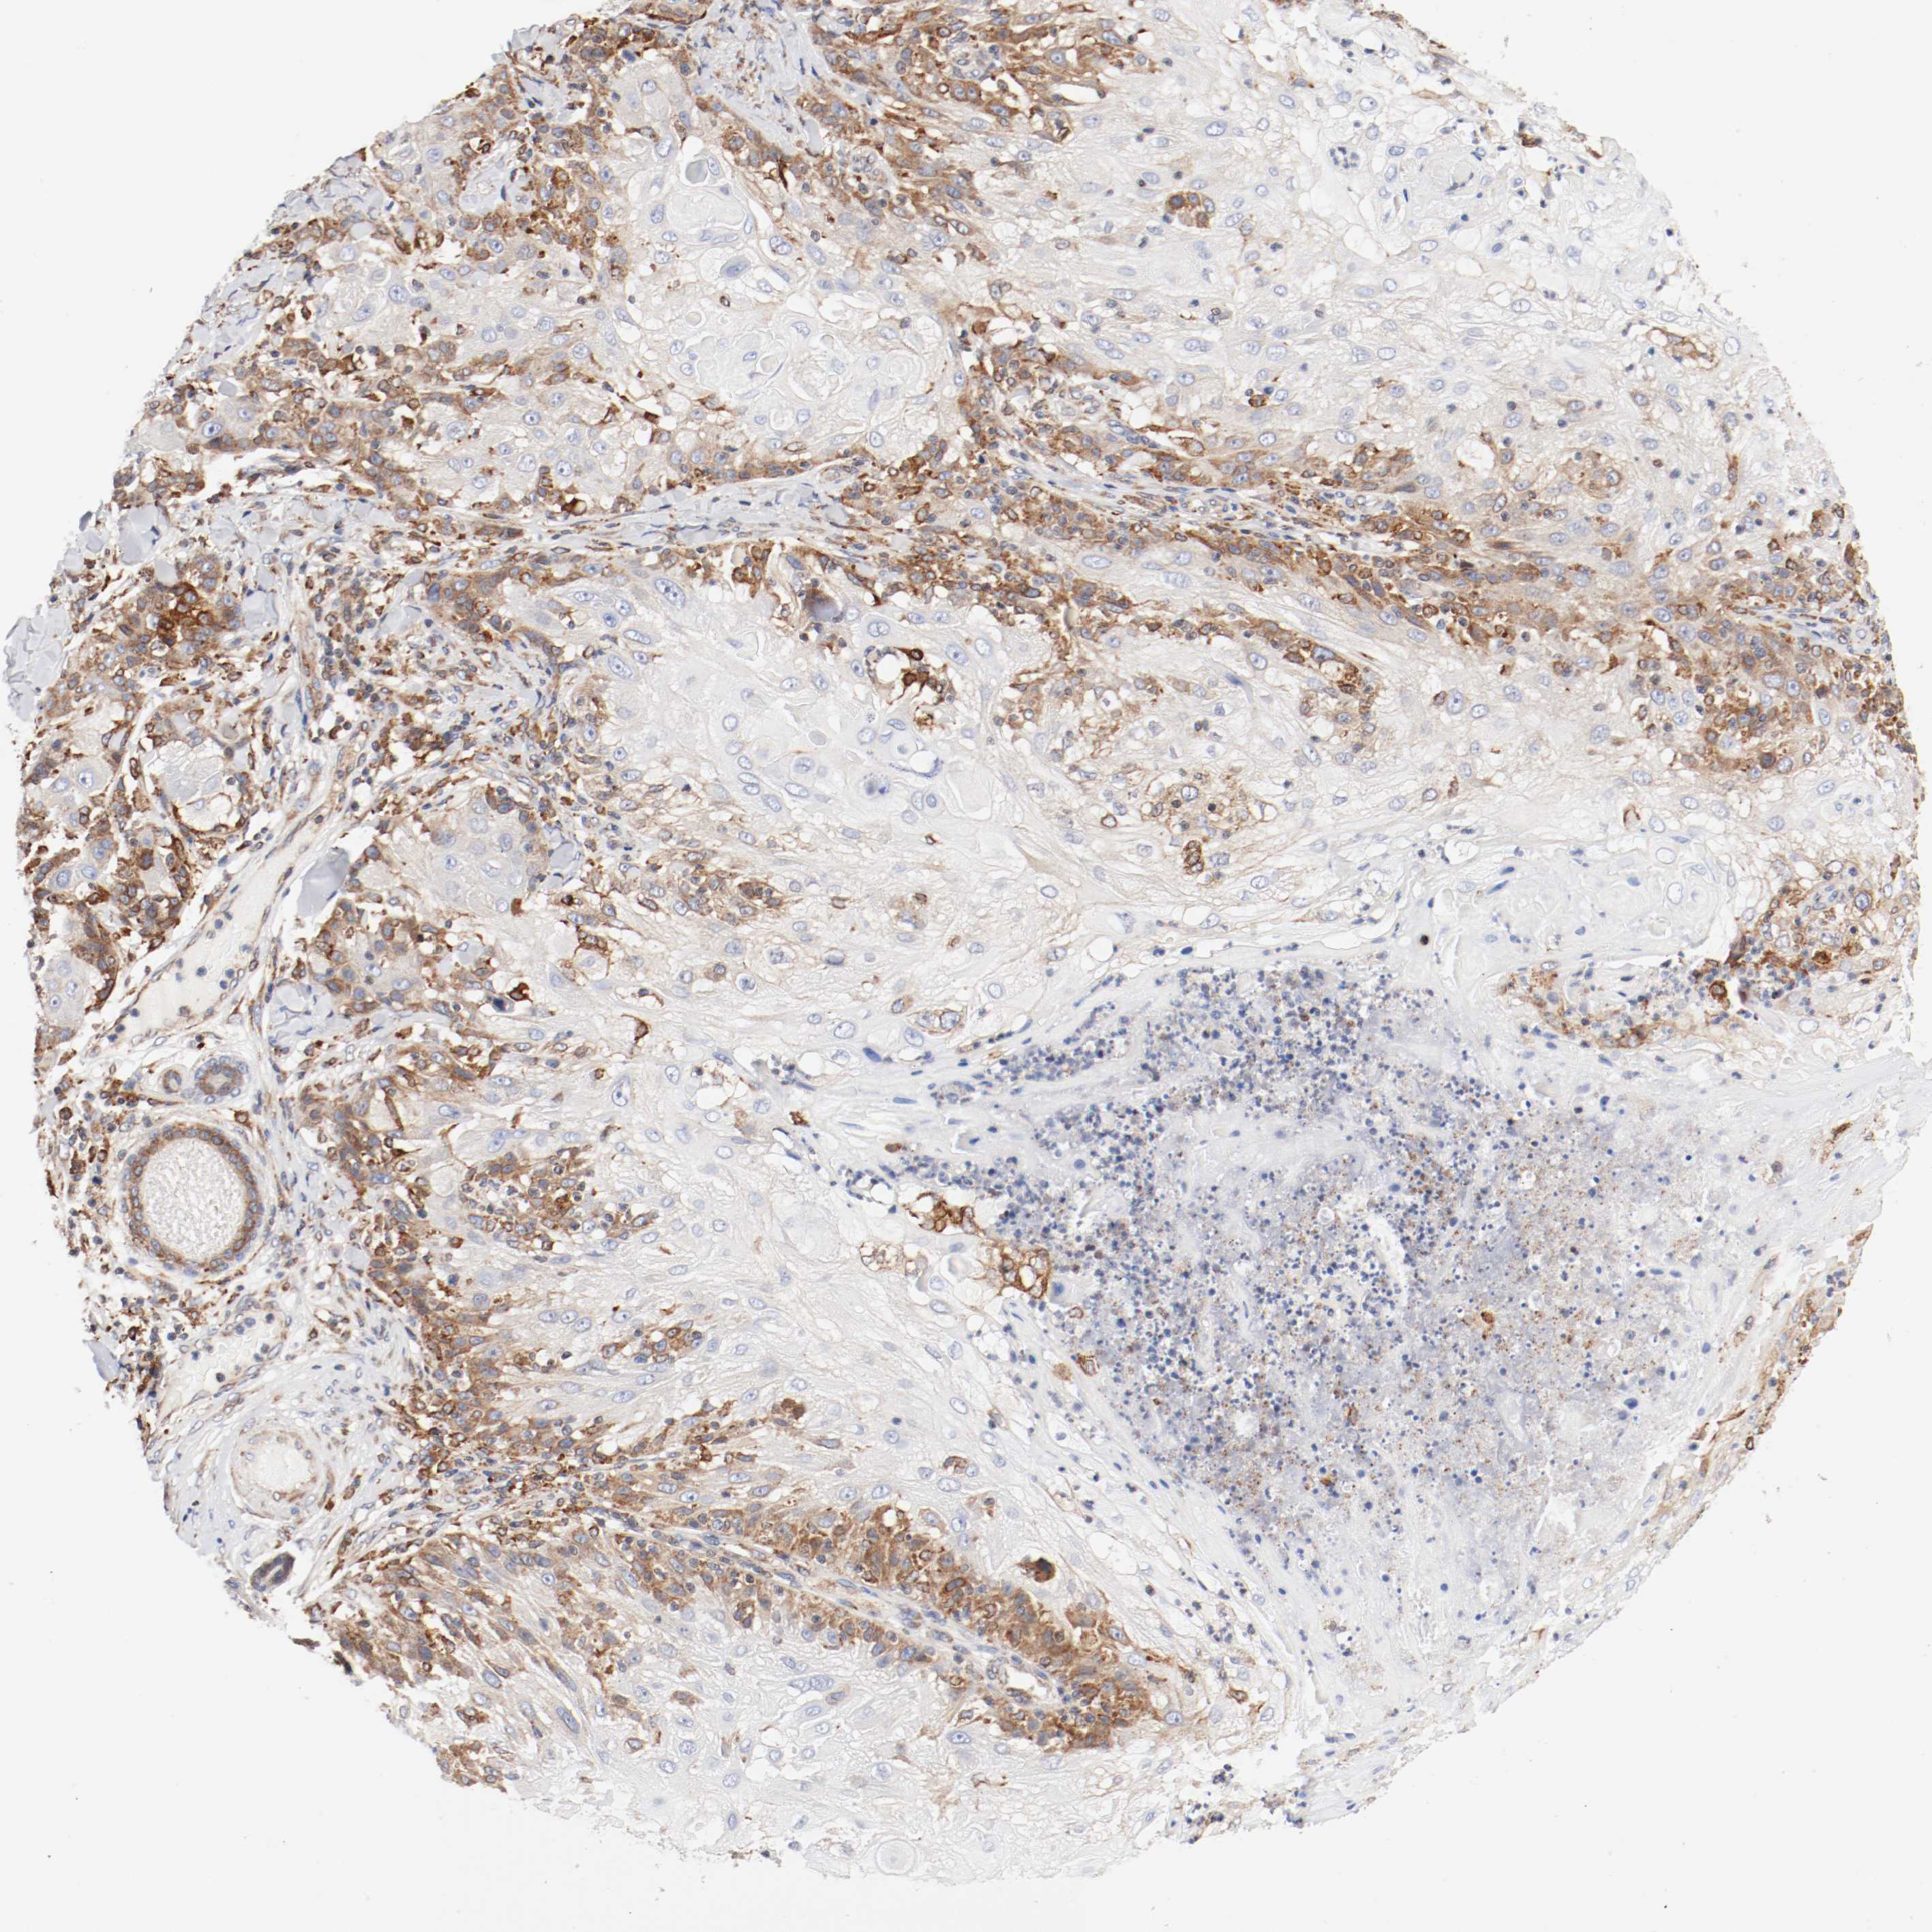

SKIN CANCER - Protein expressioni

A mouse-over function shows sample information and annotation data. Click on an image to view it in a full screen mode. Samples can be filtered based on level of antibody staining by selecting one or several of the following categories: high, medium, low and not detected. The assay and annotation is described here.

Antibody stainingi

Antibody staining in the annotated cell types in the current human tissue is reported as not detected, low, medium, or high, based on conventional immunohistochemistry profiling in selected tissues. This score is based on the combination of the staining intensity and fraction of stained cells.

Each image is clickable and will lead to virtual microscopy that enables deeper exploration of all samples and also displays staining intensity scores, fraction scores and subcellular localization as well as patient and tissue information for each sample.

Antibody HPA035199

Antibody CAB004272

Staining

High

Medium

Low

Not detected

Intensity

Strong

Moderate

Weak

Negative

Quantity

>75%

75%-25%

<25%

None

Location

Nuclear

Cytoplasmic/membranous

Cytoplasmic/membranous,nuclear

Basal cell carcinoma

Squamous cell carcinoma, NOS